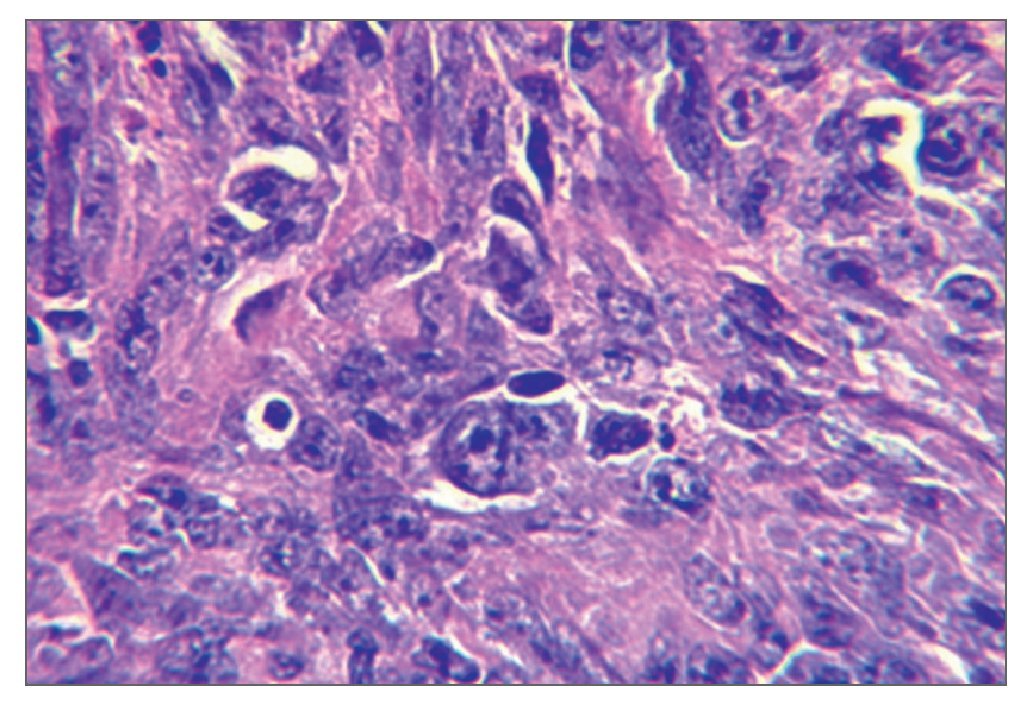

El examen histológico mostró un fuerte infiltrado difuso constituido por células blásticas linfoides grandes que presentaban núcleos ovoides y nucleolos prominentes, con presencia de numerosas mitosis atípicas (figs. 2a y 2b). La inmunohistoquímica mostró células pleomórficas positivas para CD20 y negativas para CD30, CD3, y anticuerpos Alk, confirmando el diagnóstico de LNH difuso de células B grandes (figs. 2c a 2f). Una vez completado el estudio se descartó linfoma sistémico.

Figura 2a. Infiltrado difuso de células blásticas con núcleos ovoides y nucleolos prominentes (hematoxilina-eosina; 40 aumentos originales).